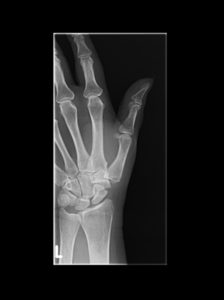

Eines dieser Verfahren ist der Einsatz einer Daumensattelgelenksprothese (Duokopfprothese). Sie hat anderen Eingriffen gegenüber wesentliche Vorteile, da Ihre Hand nach der Operation wieder schneller beweglich sein wird. Zudem verbessert sich Ihre Griffkraft und Sie werden schneller arbeitsfähig sein.

Rhizarthrose Behandlung mit einer Daumensattel-Gelenksprothese